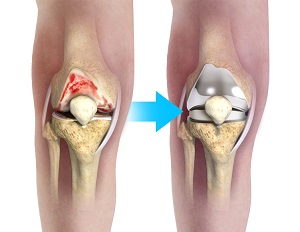

Total knee replacement, also called total knee arthroplasty, is a surgical treatment for painful arthritis of the knee in which the worn-out or damaged surfaces of the knee joint are removed and replaced with an artificial prosthesis.

In these circumstances, a complex total knee replacement affords a variety of features and benefits, such as utilizing more complex prosthetic parts with longer stems to ensure the component is securely fitted in the cavity. Some components may interlock like a hinge at the front of the knee to provide more stability. In addition, larger plastic liners, and bone grafting are often required to ensure correct alignment and length of the lower leg, replace absent bone stock, and to sufficiently restore the collateral ligaments and other soft tissue structures.